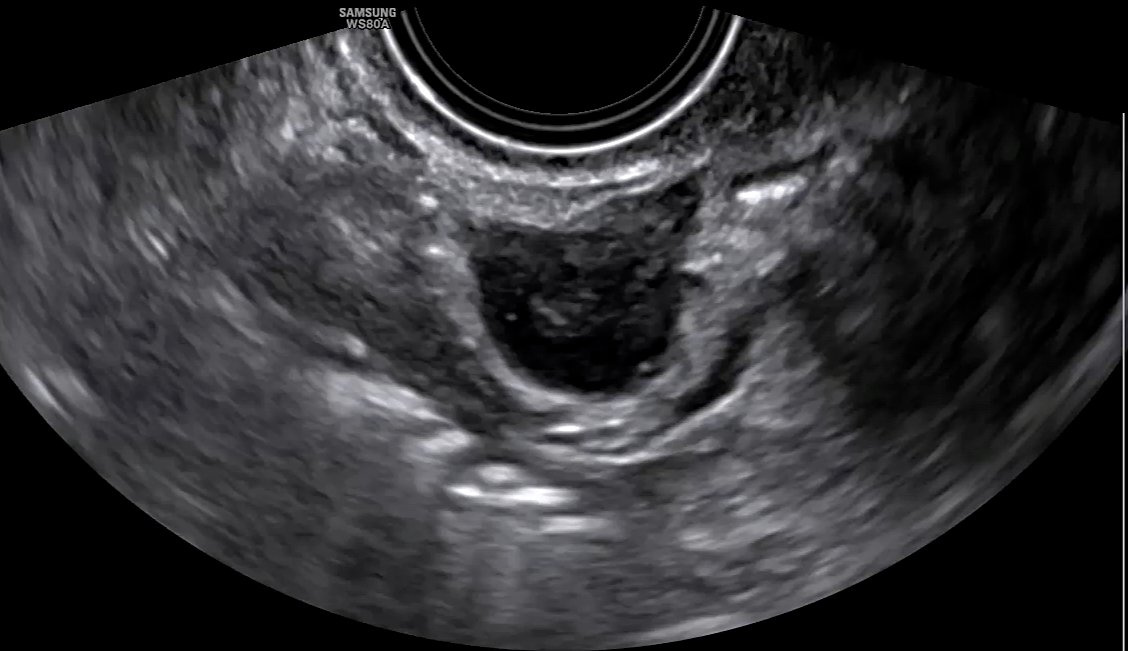

27

Ultrasound images of atypical endometrioma, with the presence of a non-vascularized papillary projection.